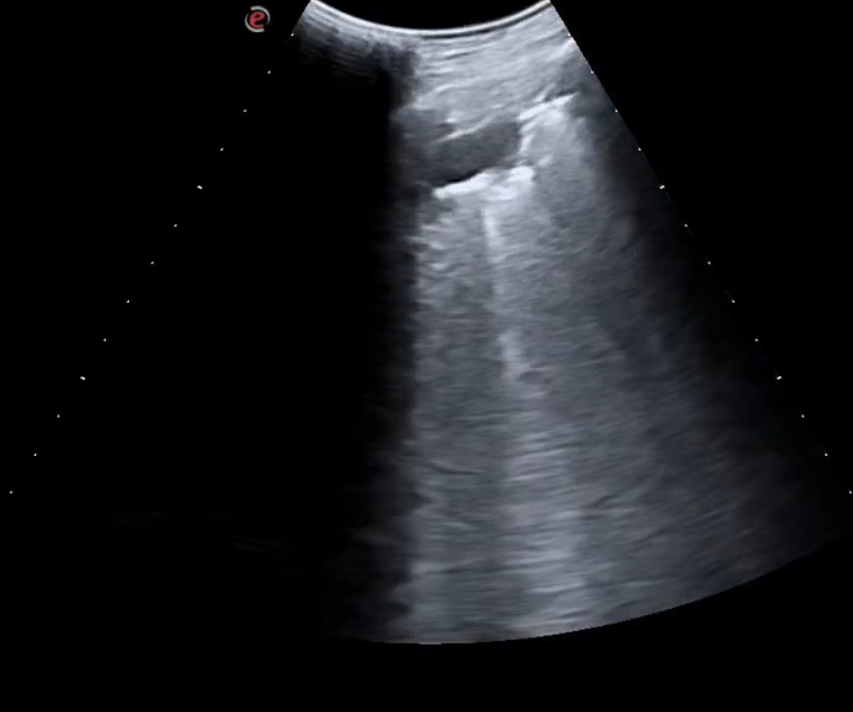

Se realiza ecografía clínica pulmonar observándose un patrón de consolidación en segmento 6 de pulmón derecho con líneas B acompañantes (mayor a 3).

Se revisó a los 15 días y el paciente presentaba una mejoría clínica, repitiéndose la ecografía y mostrando mejoría ecográfica sin presentar líneas B ni datos de condensación.

La ecografía clínica pulmonar es una herramienta muy sensible y específica que nos permite identificar lesiones que no llegan a ser visibles en la radiografía. La reproducibilidad de la técnica nos permite valorar la evolución del paciente en la propia consulta.